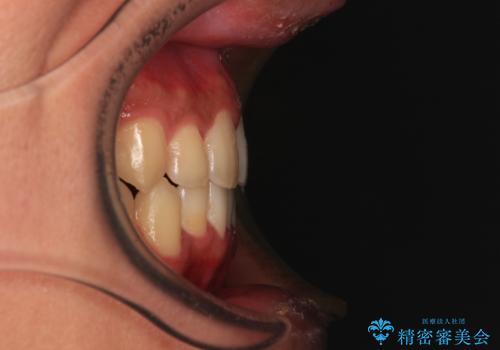

前歯のクロスバイト インビザラインによる矯正治療

- 上下のクロスバイトと前歯のデコボコを気にして来院された患者様です。

インビザラインを用い、IPR(歯と歯の間を削る)と歯列全体を拡大させることで、歯並びを整えていくこととしました。